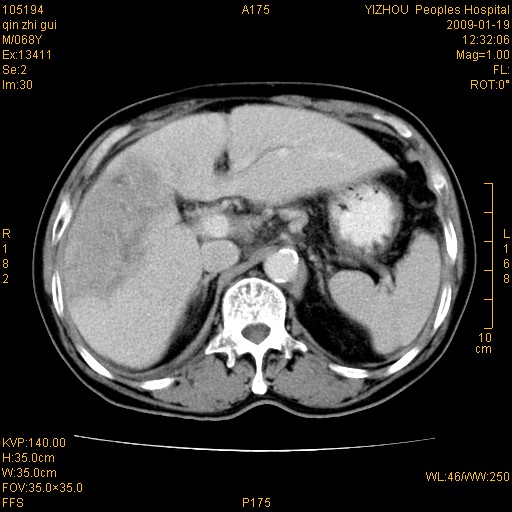

以下是引用随光逐影在2009-1-21 16:11:00的发言:[br]1)考虑肝右叶肝癌并肝静脉及门静脉瘤栓形成。2)肝硬化,少量腹水。3)胆囊炎。4)右侧少量胸腔积液。

病灶外缘凹凸不平,平扫低密度,增强动脉期有强化,门脉早显,静脉期及延期呈延迟强化,结合病史考虑右肝前叶巨块型肝癌可能性大,强化表现不除外胆管细胞癌